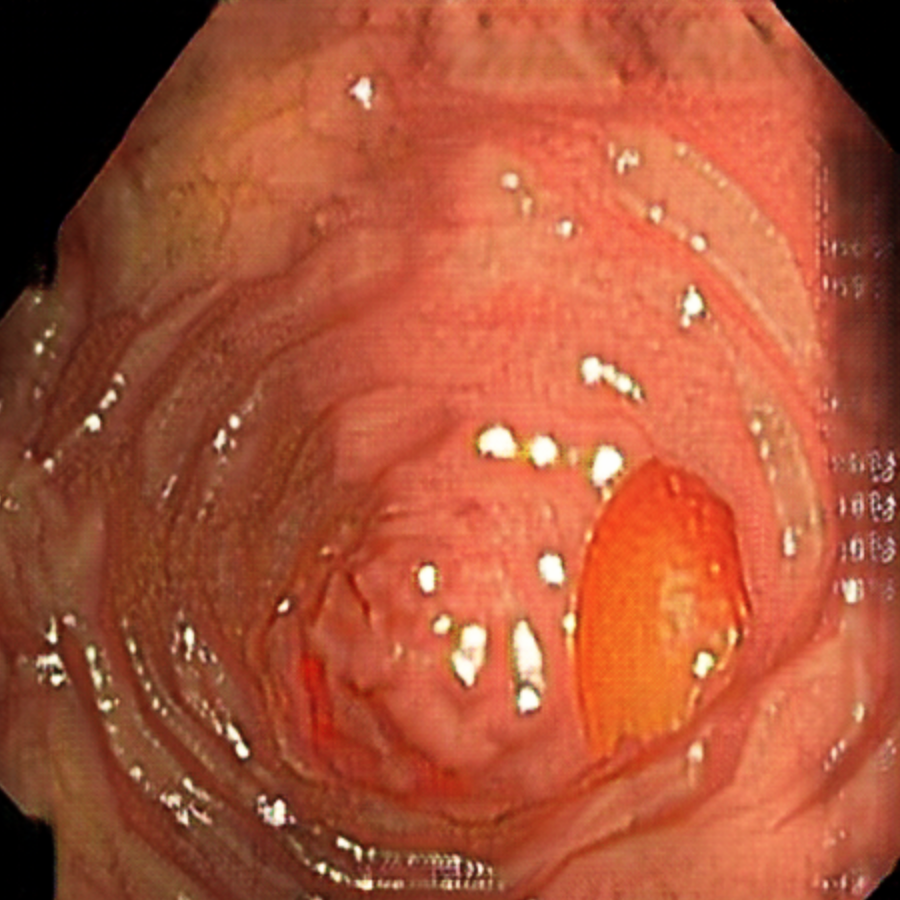

Early polyp segmentation was based in the texture and shape of the polyps. For example, Hwang et al. [8] used ellipse fitting techniques based on shape. However, some corectal polyps can be small (5mm) and are not detected by these techniques. In addition, the texture is easily confused with other tissues in the colon as can be seen in Figure 2.

With the rise of convolutional neural networks (CNNs) [10] the problem of the texture and shape of the polyps was solved and the accuracy was substantially increased. Several authors have applied deep convolutional networks to the polyp segmentation problem. Brandao et al. [2] proposed to use a fully convolutional neural network based on the VGG [16] architecture to identify and segment polyps. Unfortunately, the small datasets available and the large number of parameters make these large networks prone to overfitting. Zhou et al. [22] used an encoder-decoder network with dense skip pathways between layers that prevented the vanishing gradient problem of VGG networks. They also significantly reduced the number of parameters, reducing the amount of overfitting. More recently, Chao et al. [3] reduced the number of shortcut connections in the network to speed-up inference time, a critical issue when performing real-time colonoscopies in high-resolution. They focused on reducing the memory traffic to access intermediate features, reducing the latency. Finally, Huang et al. [7] improved the performance and inference time by combining HarDNet [3] with a cascaded partial decoder [21] that discards larger resolution features of shallower layers to reduce latency.